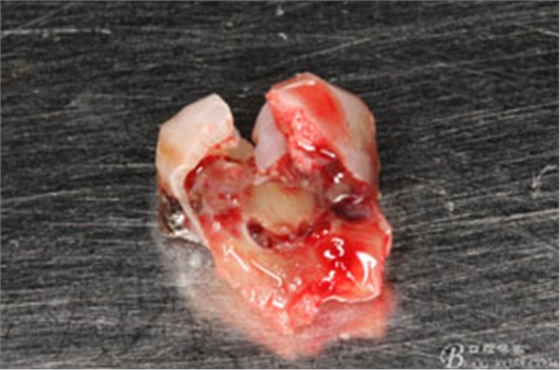

圖8.拔除的37頰側(cè)的牙根完全被壓迫吸收完

各種位置的埋伏牙常常會壓迫臨近牙齒的牙根吸收,導(dǎo)致鄰牙被拔除。多見于上頜埋伏尖牙壓迫中切牙牙根吸收、下頜埋伏智齒導(dǎo)致第二磨牙牙根吸收等等,所以提示我們口腔醫(yī)生要注意埋伏的診治。本病例是一例多生牙壓迫37牙根吸收,導(dǎo)致37被拔除,實屬少見。